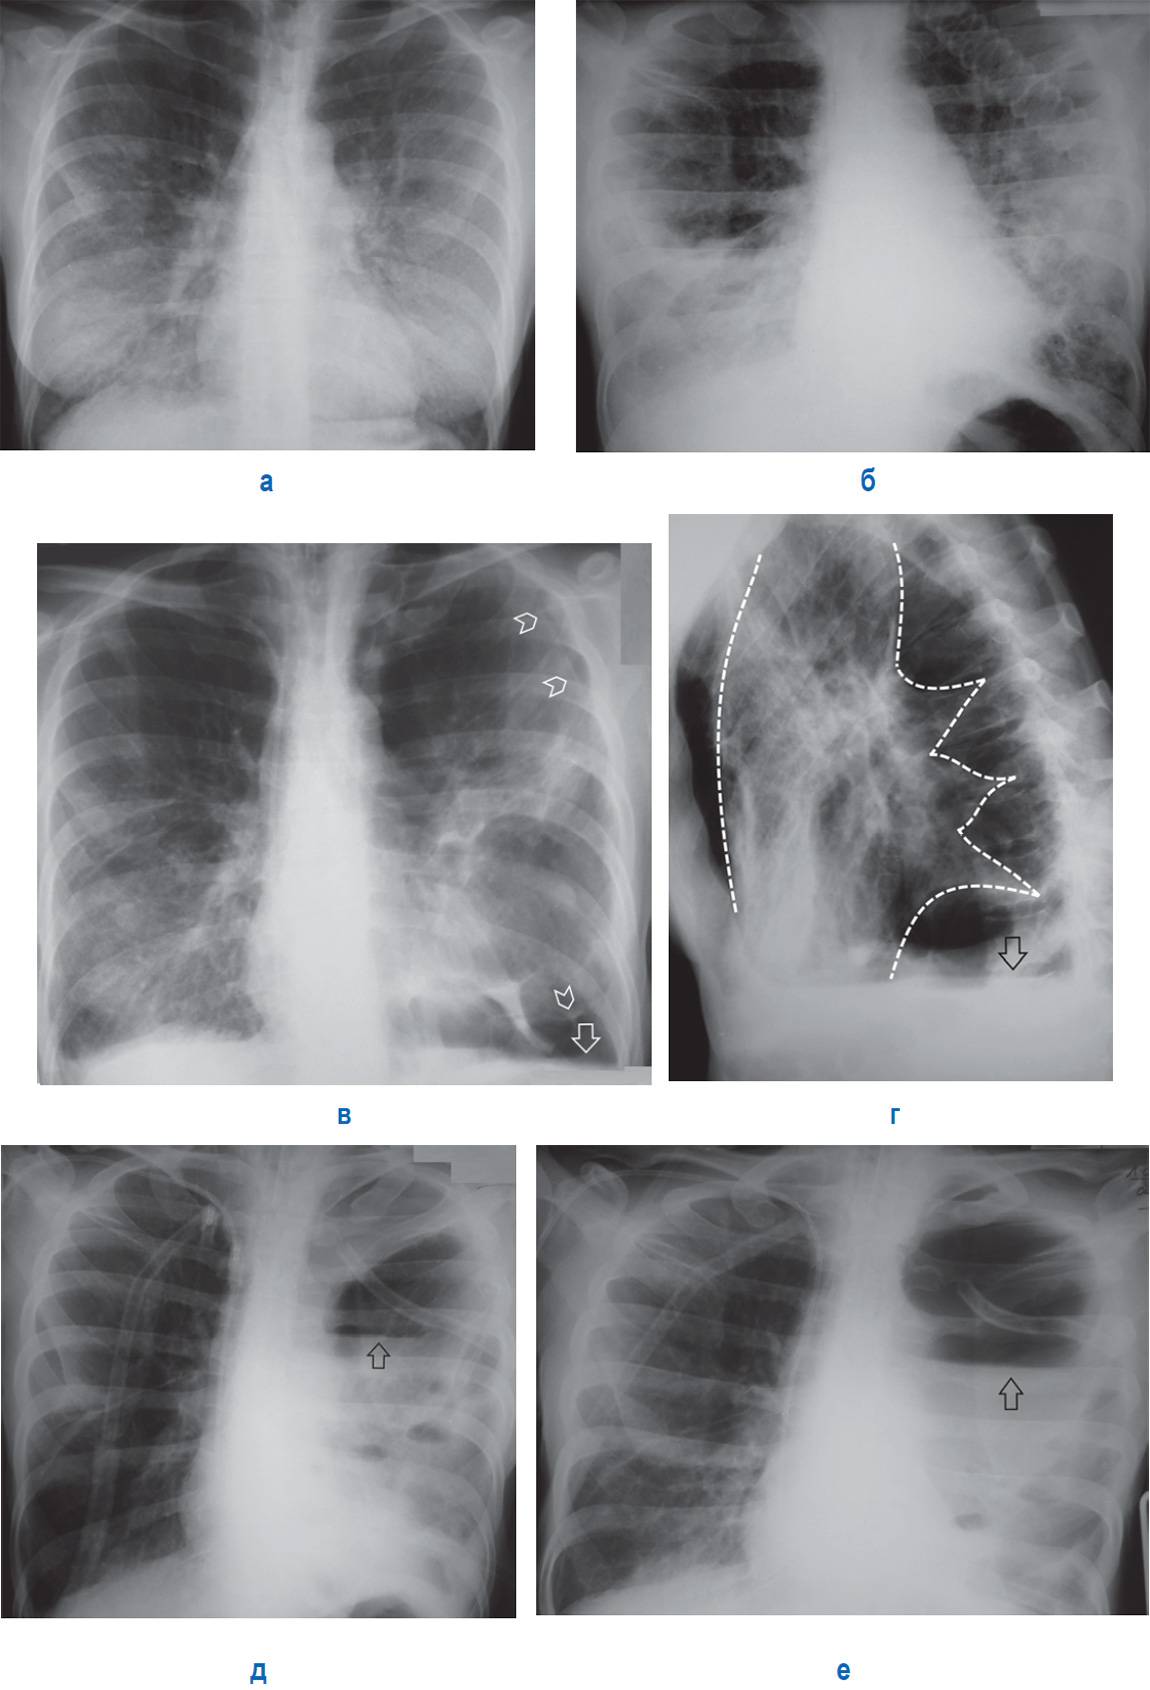

Поражение легких является одним из основных симптомов коронавируса (COVID-19). В данной статье представлены фото рентгеновских снимков, которые позволяют визуально оценить состояние легких при этом заболевании.

На фотографиях рентгеновских снимков видно, как вирус воздействует на легочную ткань. Характерные признаки поражения легких включают пятна, инфильтраты и наличие жидкости внутри легочных альвеол.

Фото рентгеновских снимков помогают врачам и специалистам визуально определить степень поражения легких и принять соответствующие меры лечения и поддержки пациента.